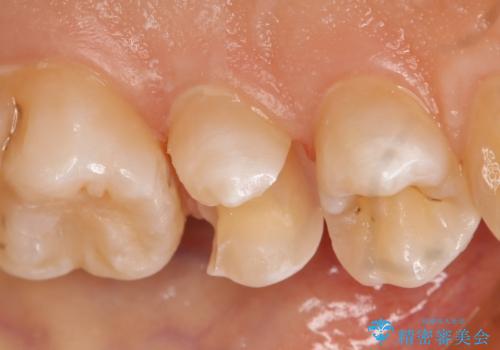

- 左上5番の虫歯治療を主訴に来院された患者様です。

セラミックでの治療を希望されたので形態・切削量を考慮しセラミックインレーでの治療を選択しました。

隣り合っている面(隣接面)は清掃がしづらく虫歯になりやすい場所です。

また、形態の再現が難しいのでインレーなどの補綴物での治療が第一選択となることが多いです。